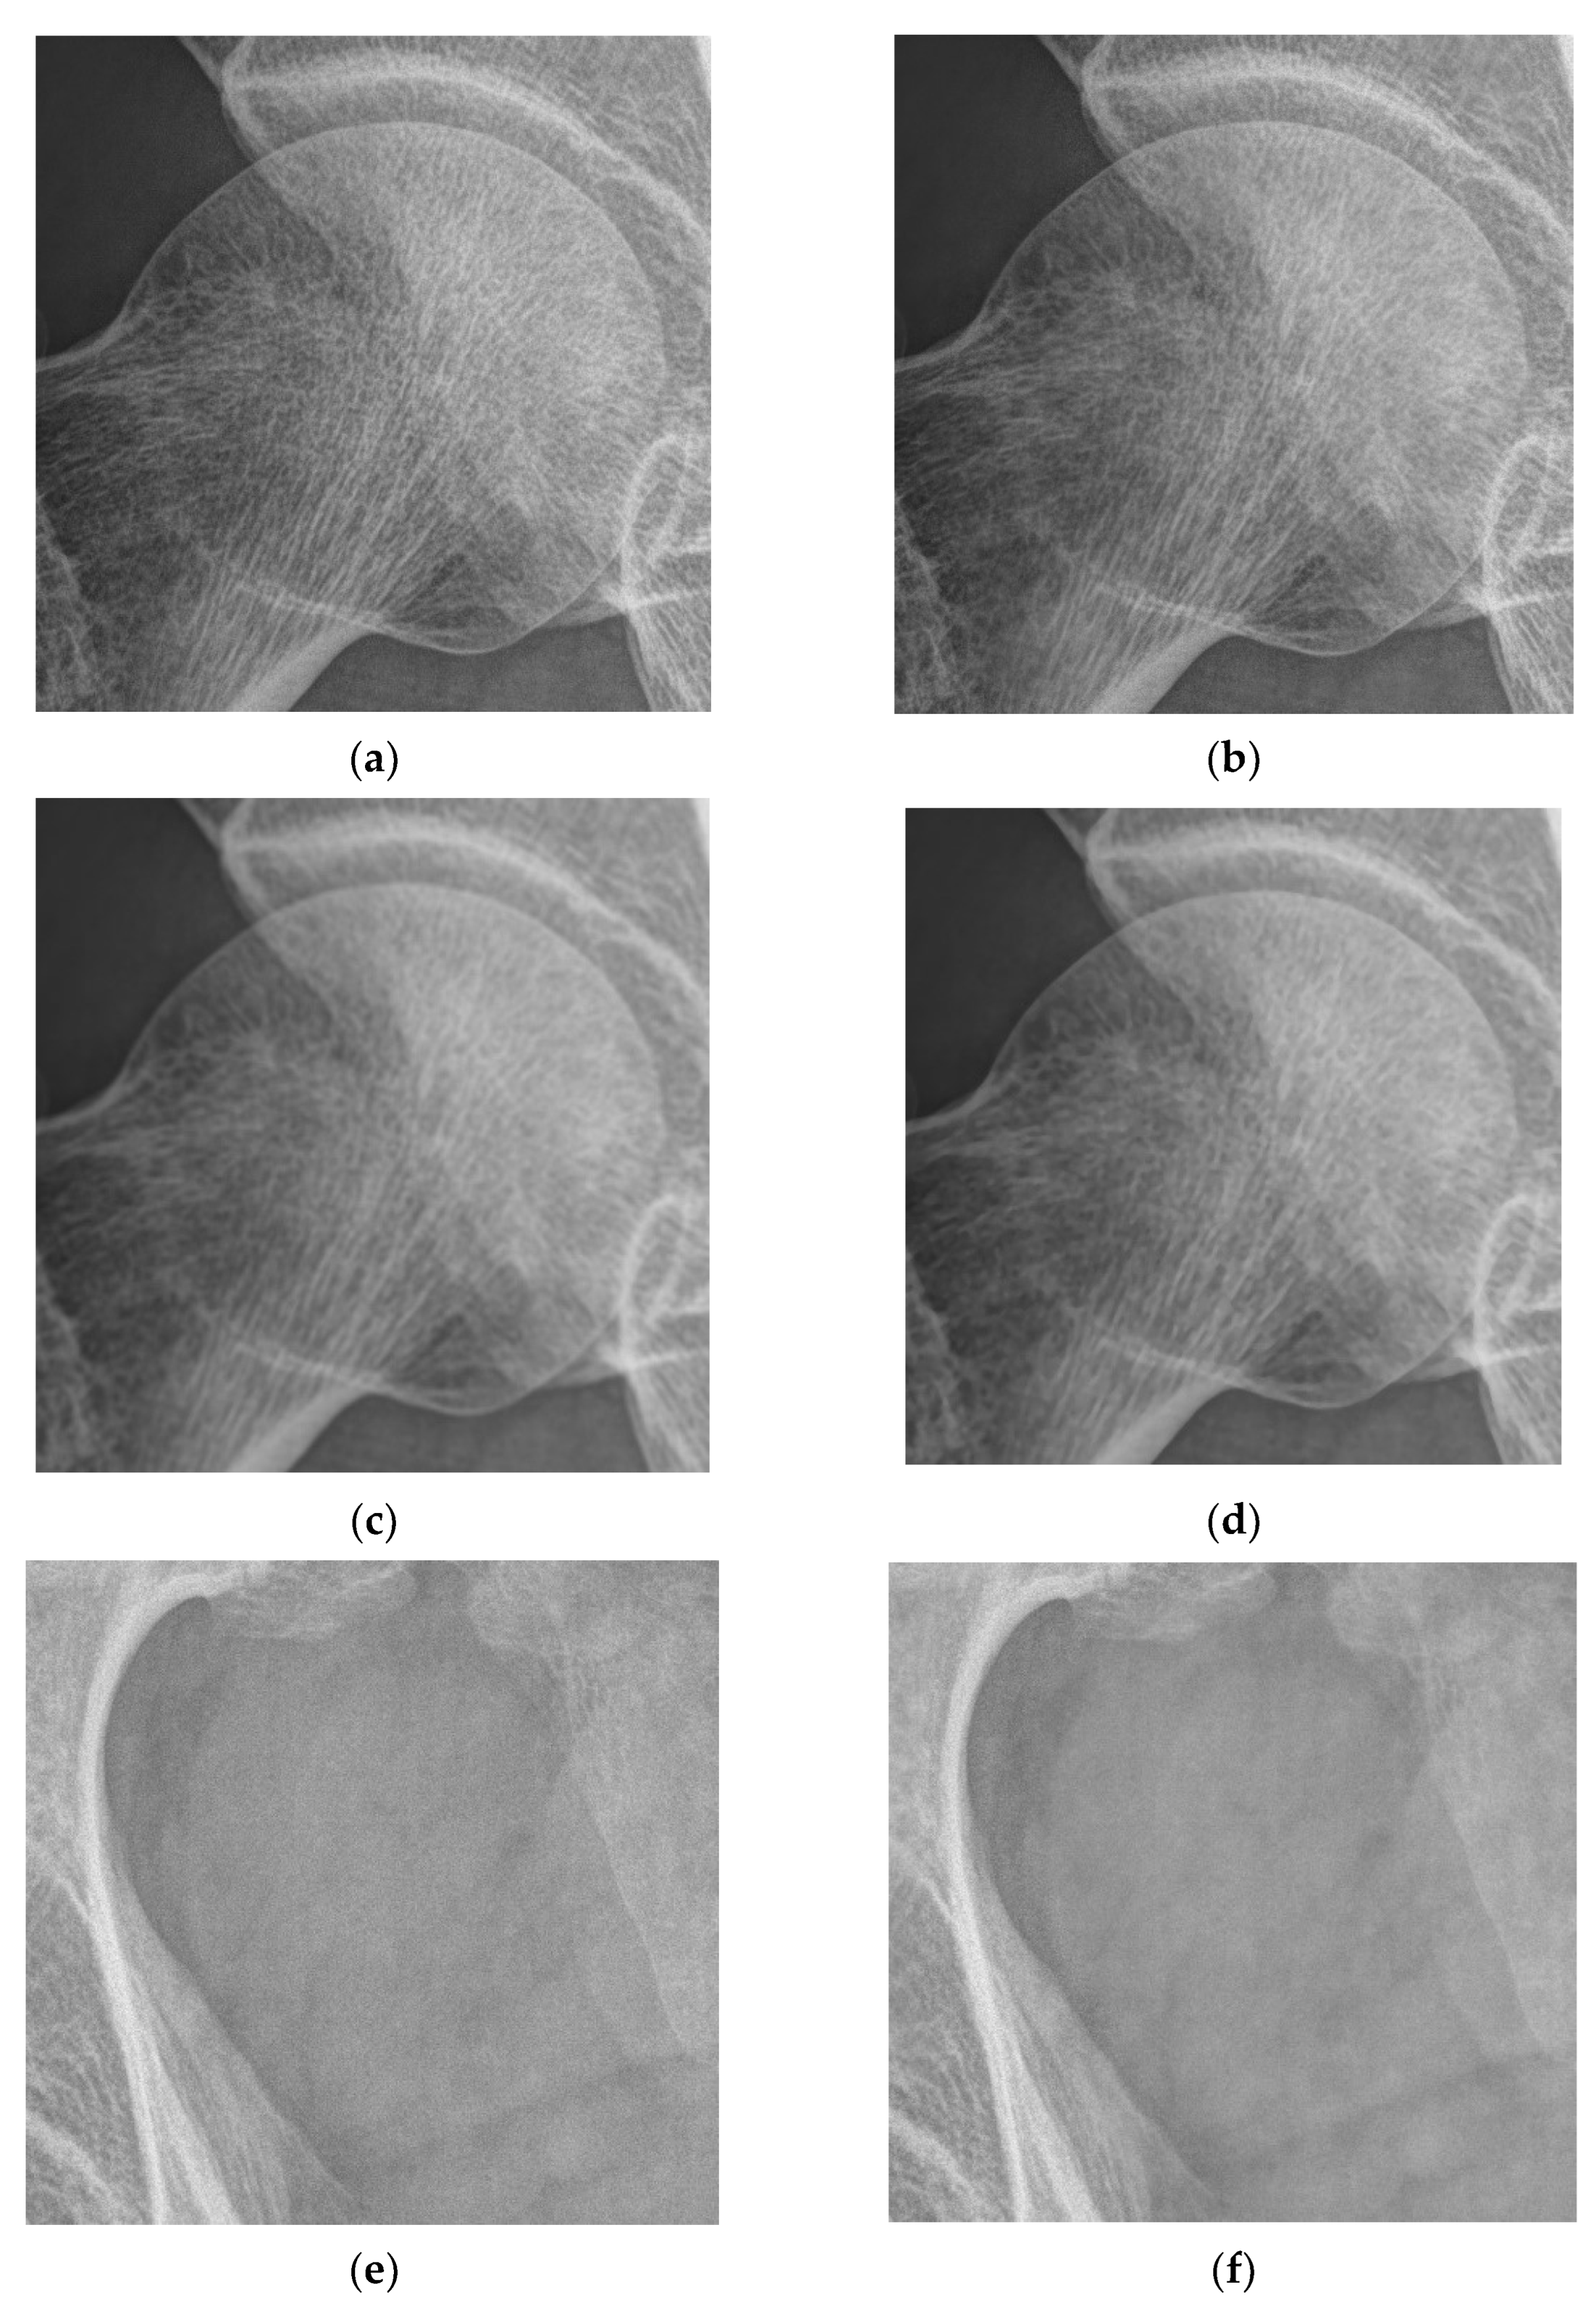

4.1. Simulations for Multicale Diagnostic Detail Enhancement on DR Images